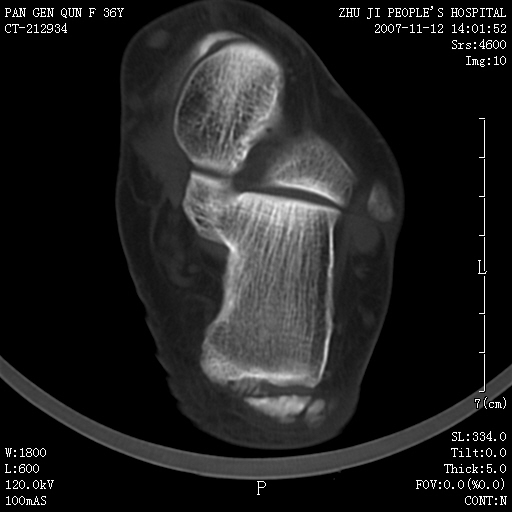

标题: CT10417:F36Y,跟骨跟腱附着处下方骨质密度影,请会诊. [打印本页]

标题: CT10417:F36Y,跟骨跟腱附着处下方骨质密度影,请会诊.

跟骨结节后部肿块半年,无明确外伤史,及红肿热痛.

附丽病

附丽病:是指肌腱、关节囊、韧带于骨附着处的骨化和骨质侵蚀改变,常见于坐骨结节、髂骨嵴、坐骨耻骨支、股骨大小粗隆、跟骨结节等处。

x线表现为具有骨密度的细条索状影自骨面伸向附近的韧带、肌腱,宛如浓厚的胡须,以病变晚期更为明显,并有局部骨质侵蚀。